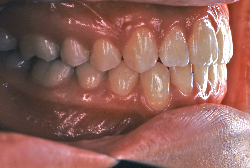

凸凹な歯並びのことを叢生といいます。矯正歯科に来院する患者様の主訴の中で、最も多いのが「配列の凸凹を真っ直ぐにしたい」というものです。歯の大きさと顎の大きさの調和がとれていないことが原因です。

凸凹を主体としたケースの場合、当院の平均治療期間は18ヶ月ですので、このケースは少し長めに経過しました。理由の一つは凸凹の程度がかなり重症だったと言うことですが、もう一つは、右下第2大臼歯が45度くらい前傾していたため、それを整直化させるために時間を要したと考えています。いずれにしても最終結果は大変よい状態と思います。

治療前は並びが乱れて見た目が悪いというのはもちろん問題ですが、歯科医学的に一番困るのは噛み合わせが悪いという点です。上下の犬歯(3番目の歯)は、上下的に離れた位置にあるため接触することができません。つまり歯としては存在していても、歯としては機能していないということです。